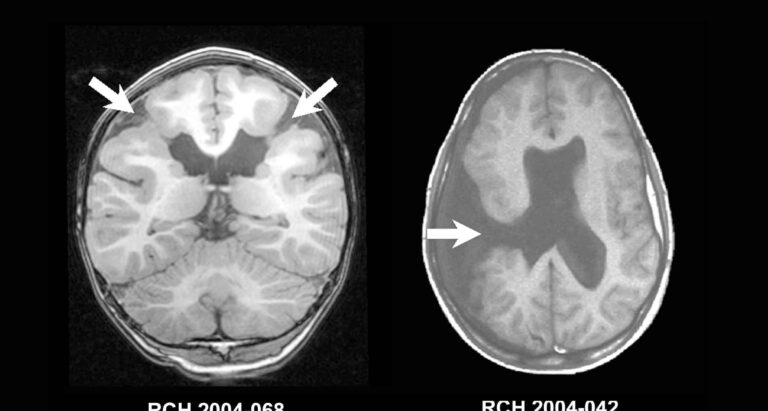

Porencefalia – Vídeo de Ultrassom

<span data-mce-type=”bookmark” style=”display: inline-block; width: 0px; overflow: hidden; line-height: 0;” class=”mce_SELRES_start”></span><span data-mce-type=”bookmark” style=”display: inline-block; width: 0px; overflow: hidden;…